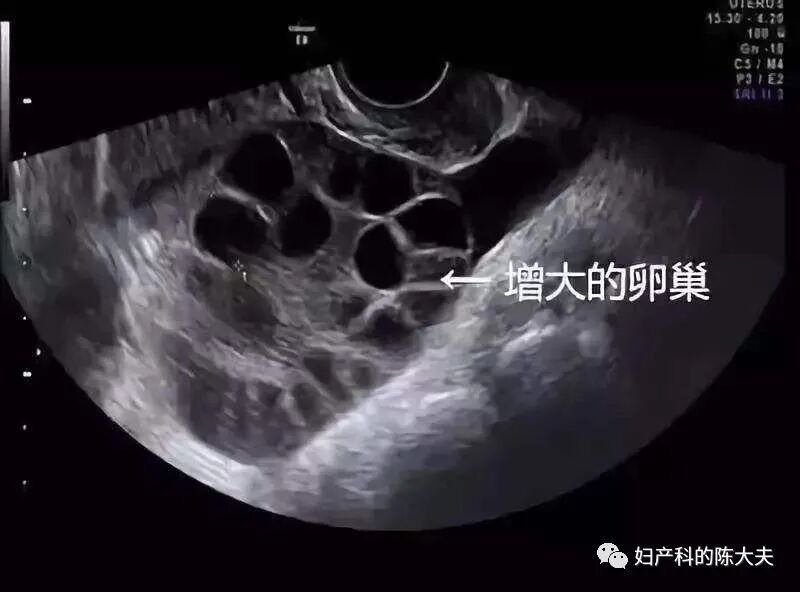

女性每个生理周期只能1-2枚卵子,对试管婴儿这个操作来说显然是不够的,所以在取卵之前,得先促排卵。促成2个及以上卵泡发育。

从这一步开始,就体现医生的水平了。因为促少了没有,促多了会发生卵巢过度刺激综合症。这是一个很恐怖的疾病,极端情况未经及时抢救会屎。